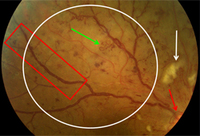

Non-proliferative diabetic retinopathy: intraretinal microvascular abnormality (IRMA; green arrow), venous beading and segmentation (blue arrow), cluster haemorrhage (red circle), featureless retina suggestive of capillary non-perfusion (white ellipse)

Courtesy of Moorfields Photographic Archive; used with permission